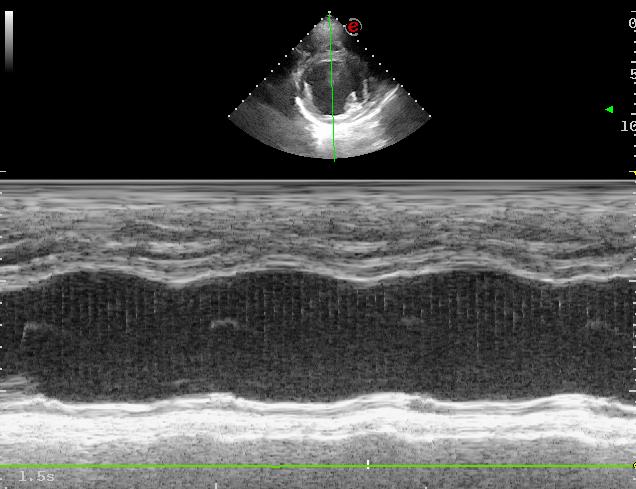

Issuu converts static files into: digital portfolios, online yearbooks, online catalogs, digital photo albums and more. Sign up and create your flipbook.